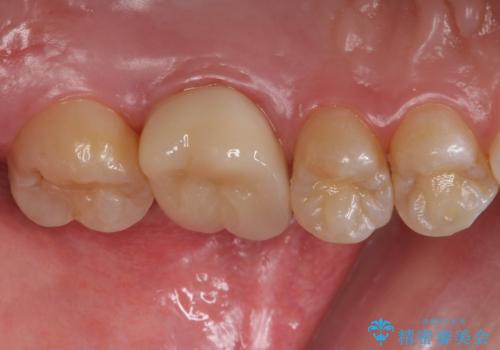

- 左上6:仮歯+ジルコニアクラウン/11,000円+121,000円 , 再根管治療(リトリートメント)+土台(ファイバーコア)/143,000円+22,000円費用は治療当時の料金となります

本来は歯茎をしっかりと下げる外科処置が適応となるケースでしたが、ご希望がなかったため最小限の侵襲に抑えて治療を行いました。

根の中を洗浄し、結果的に適合の良い被せ物をセットすることができました。